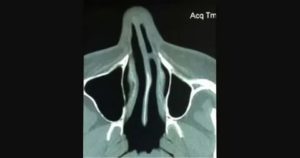

Передние синехии полости носа могут быть диагностированы отоларингологом при осмотре пациента. Средние и задние синехии полости носа выявляются при проведении риноскопии. Вид синехий (костные, хрящевые или соединительнотканные) устанавливают при помощи их прощупывания пуговчатым зондом.

Для диагностики сопутствующих воспалительных изменений проводят также фарингоскопию, ларингоскопию, исследование проходимости слуховой трубы, отоскопию, исследование околоносовых пазух (рентгенографию, КТ, УЗИ). Установить этиологию выявленных воспалительных заболеваний помогает проведение бак.

исследования мазков из зева и носа.

Если соединительные ткани расположены в передней части носа, их легко сможет выявить ЛОР при осмотре пациента риноскопом. Также проводится обследование и синехий, локализующихся в средней или задней части носовой полости. Для определения типа ткани соединительного образования, синехии прощупывают специальным пучковатым зондом.

Если необходимо диагностировать воспаления, которые возникли в результате образования синехий, тогда проводят фаринго- и ларингоскопию. В тех случаях, когда есть подозрения на поражение евстахиевой трубы, нужно провести исследование на проходимость слухового канала с помощью отоскопии.

Для диагностики состояния придаточных пазух проводят рентгеноскопию, КТ или МРТ. Установить причины воспаления поможет бактериальное исследование мазков, взятых из носовой полости и зева.